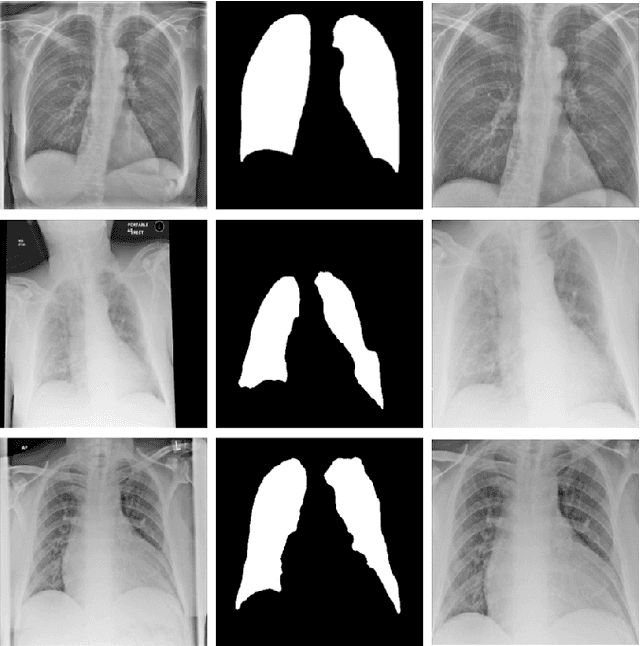

Abstract:During the COVID-19 pandemic, the sheer volume of imaging performed in an emergency setting for COVID-19 diagnosis has resulted in a wide variability of clinical CXR acquisitions. This variation is seen in the CXR projections used, image annotations added and in the inspiratory effort and degree of rotation of clinical images. The image analysis community has attempted to ease the burden on overstretched radiology departments during the pandemic by developing automated COVID-19 diagnostic algorithms, the input for which has been CXR imaging. Large publicly available CXR datasets have been leveraged to improve deep learning algorithms for COVID-19 diagnosis. Yet the variable quality of clinically-acquired CXRs within publicly available datasets could have a profound effect on algorithm performance. COVID-19 diagnosis may be inferred by an algorithm from non-anatomical features on an image such as image labels. These imaging shortcuts may be dataset-specific and limit the generalisability of AI systems. Understanding and correcting key potential biases in CXR images is therefore an essential first step prior to CXR image analysis. In this study, we propose a simple and effective step-wise approach to pre-processing a COVID-19 chest X-ray dataset to remove undesired biases. We perform ablation studies to show the impact of each individual step. The results suggest that using our proposed pipeline could increase accuracy of the baseline COVID-19 detection algorithm by up to 13%.